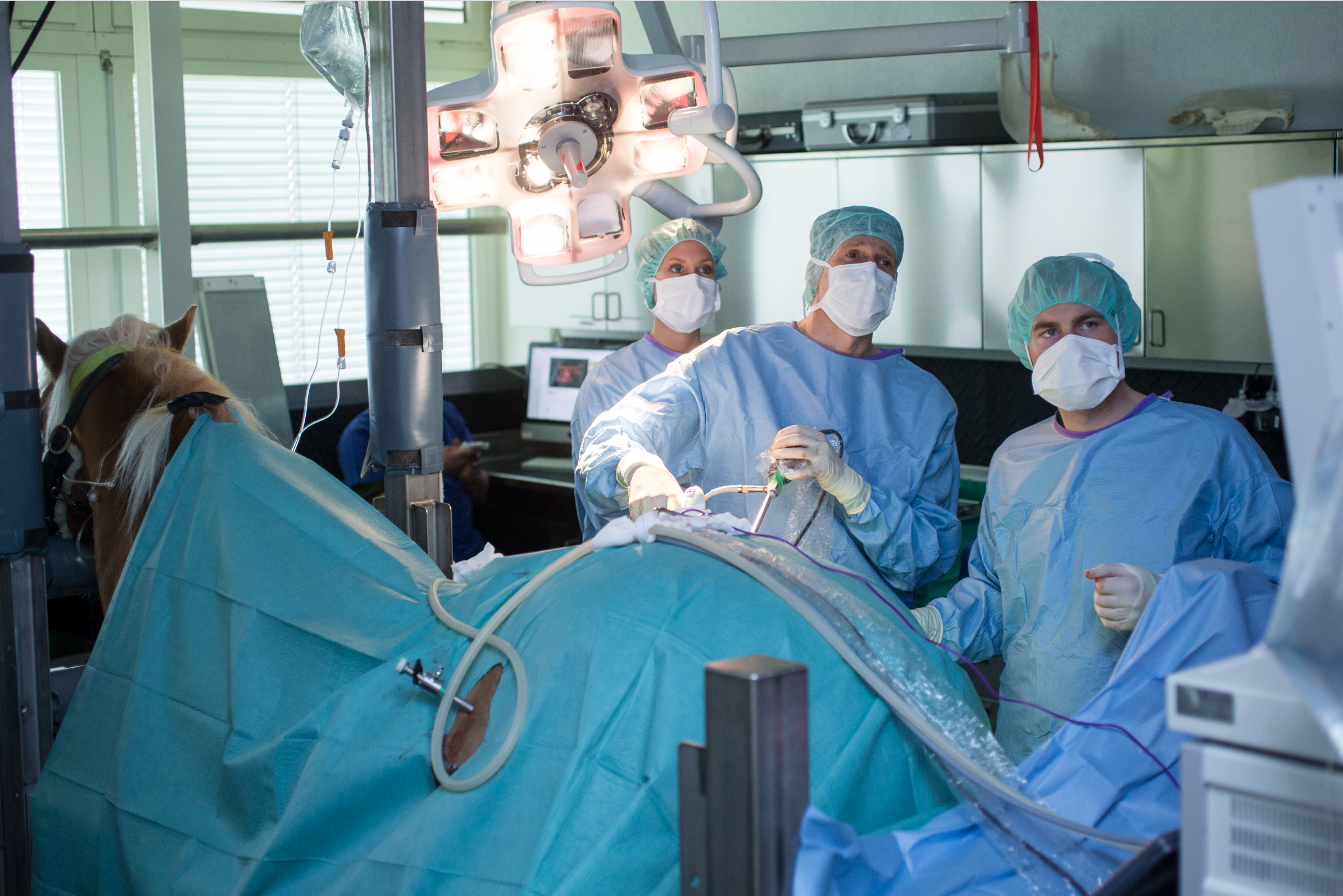

Die Behandlung der Wahl ist eine chirurgische Eierstock Entfernung (Ovariektomie). Es gibt verschiedene chirurgische Verfahren, die zur Entfernung des Eierstocks verwendet werden können. Meistens wird die Ovariektomie laparoskopisch (d.h. minimal invasiv mit einer Kamera und speziellen Geräten) über einen Zugang in der Flanke bei stehendem und sediertem Pferd durchgeführt. Dieser Ansatz ist vorteilhaft, weil er dem Chirurgen einen besseren Zugang zu den Eierstöcken und deren Blutversorgung für die Entfernung ermöglicht und eine Vollnarkose vermeidet.

Der Patient wird in den Untersuchungsstand gebracht und sediert. Nachfolgend wird das Operationsfeld ausgeschoren, gereinigt und desinfiziert. Die Chirurgen decken das Pferd mit sterilen Tüchern ab und setzten eine Lokalanästhesie an den gewünschten Zugängen zur Bauchhöhle.

Die Operationstechnik gleicht der Arthroskopie und auch hier wird die Triangulationsmethode angewendet, bei welcher zuerst ein Portal für das Laparoskop (Stabkamera) und anschliessend unter Sichtkontrolle die Portale für die Instrumente präpariert werden. Um eine bessere Übersicht in der Bauchhöhle zu erhalten, wird diese mit CO2-Gas gefüllt und dadurch gebläht. Das Gebiet um die Ovarien wird ebenfalls lokal betäubt. Anschliessend werden die Blutgefässe mit einem Kauter (Ligasure) verschlossen und mit dem gleichen Gerät können die Eierstöcke abgesetzt werden.

Für die Entfernung der Ovarien gibt es verschiedene Techniken. Einerseits können sie über eine vergrösserte Hautinzision alleine oder in einem Bergungsbeutel entfernt werden. Wenn der Eierstocktumor dafür zu gross ist, kann dieser mit einem sogennanten Morcellator zuerst verkleinert werden, um den Tumor über die minimal invasiven Zugänge zu entfernen. Dann kann die Bauchhöhle wieder verschlossen werden und ein Wundschutz wird angebracht.